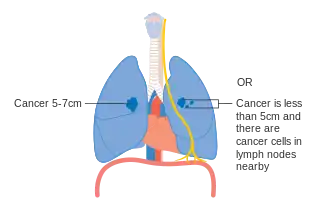

Lung cancer staging is an assessment of the degree of spread of the cancer from its original source.[77] It is one of the factors affecting both the prognosis and the potential treatment of lung cancer.[2][77]

The evaluation of non-small-cell lung carcinoma (NSCLC) staging uses the TNM classification (tumor, node, metastasis). This is based on the size of the primary tumor, lymph node involvement, and distant metastasis.[2]

Using the TNM descriptors, a group is assigned, ranging from occult cancer, through stages 0, IA (one-A), IB, IIA, IIB, IIIA, IIIB, and IV (four). This stage group assists with the choice of treatment and estimation of prognosis.[80]

SCLC has traditionally been classified as "limited stage" (confined to one-half of the chest and within the scope of a single tolerable radiotherapy field) or "extensive stage" (more widespread disease).[2] However, the TNM classification and grouping are useful in estimating prognosis.[80]

- Diagrams of main features of staging

Stage IIB lung cancer

One option for stage IIB lung cancer, with T2b; but if tumor is within 2 cm of the carina, this is stage 3